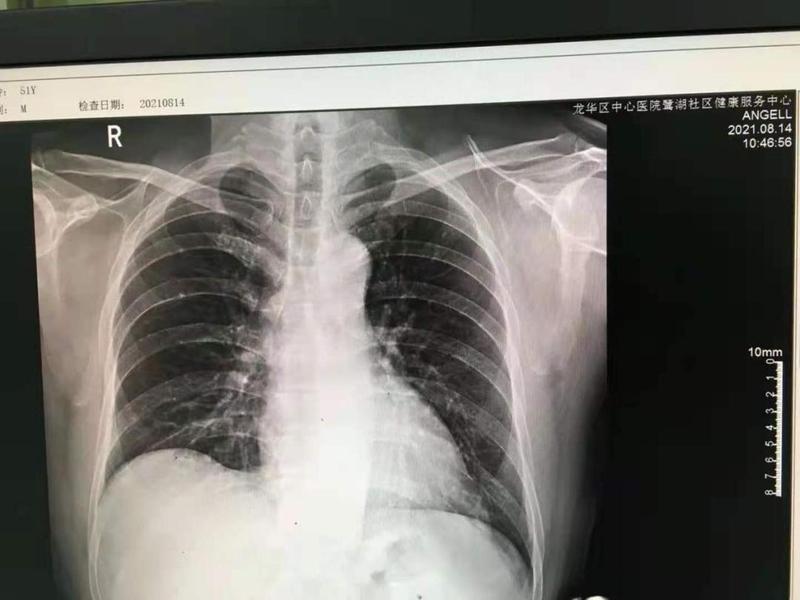

看!

这是鹭湖社康中心的第一张DR片

今年,龙华区中心医院鹭湖社康中心开始着手引进DR远程诊断系统。经过一年时间的筹备和建设,鹭湖社康中心DR远程诊断系统于近日完成并投入使用。2021年8月14日,鹭湖社康中心第一张DR片(数字化医用X射线摄影系统)也正式出炉,从此社区居民在家门口的社康中心就能拍片,不用去医院排队挂号,也能享受医院专家的诊断服务。